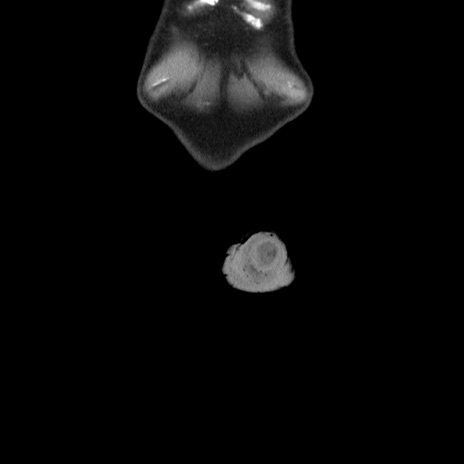

横断像